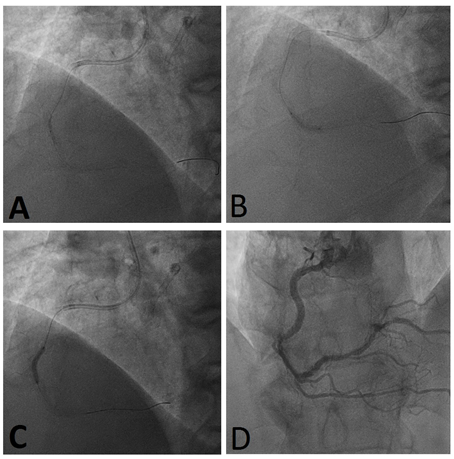

A 67-year-old man was conduct to our primary percutaneous coronary intervention (PCI) service (Catheterization Laboratory and Cardiovascular Interventional Unit, Division of Cardiology, Cannizzaro Hospital, Catania, Italy) by the paramedic ambulance team for chest pain and inferior ST-segment elevation on his electrocardiogram (ECG). He was an ex-smoker, affected by mild systemic hypertension treated with ACE-inhibitor and beta-blocker, and his medical history included a previous acute coronary syndrome (ACS) treated with PCI with a drug eluting stent (DES) on left anterior descending (LAD) artery 7years earlier. With an established diagnosis of inferior ST-segment Elevation Myocardial Infarction (STEMI), the patient was brought to our cath lab and he was loaded with 300mg of Aspirin, 180mg of Ticagrelor and 8,000 IU of unfractioned heparine prior the catheterization. Coronary angiography was performed by right radial artery access with a 6 French sheath and 6 French catheters: the angiograms showed a good result of previous LAD-PCI and a complete occlusion of the mid right coronary artery (RCA) which appears as acute event, although the artery was tortuous and heavily calcified (Figure 1). At the beginning, a 6 French Judkins Right 4.0 guiding catheter was used to engage the RCA ostium. The lesion was crossed by an extra-back Sion Blue guidewire (Asahi Intecc, Nagoya, Japan); subsequently using the “buddy wire” technique with another Sion Blue guidewire, a semi-compliant balloon 1.5/15mm was inflated in the mid RCA but no anterograde flow was achieved. Due to the poor back up support, the guiding catheter was exchange with an Amplatz Left 1.0. The lesion was easily crossed the extra-back Sion blue guidewire and multiple dilatations with 2.0/20mm and 2.5/20mm semi-compliant balloons were performed, obtaining a complete restore of anterograde flow (Thrombolysis In Myocardial Infarction 3 flow -TIMI 3 flow-) (Figure 2), resolution of chest pain and ECG signs of ischaemia/lesion. Due to the stability of the patient and the resolution of the symptoms, the operator decided to stop the procedure and the patient was schedule to perform a staged-PCI procedure using rotational atherectomy (RA).

Figure 1 Basal Coronary Angiography A) Angiogram shows occlusion of right coronary artery in a left anterior oblique projection; B) Angiogram showing good result of previous stent implantation in mid left anterior descending in antero-posterior cranial projection.

Figure 2 Primary Percutaneous Coronary Intervention for quick reopening of occluded vessel A, B, C) Angiograms showing balloon dilatation through right coronary artery from proximal to distal segments; D) Angiogram showing final result after ballooning.